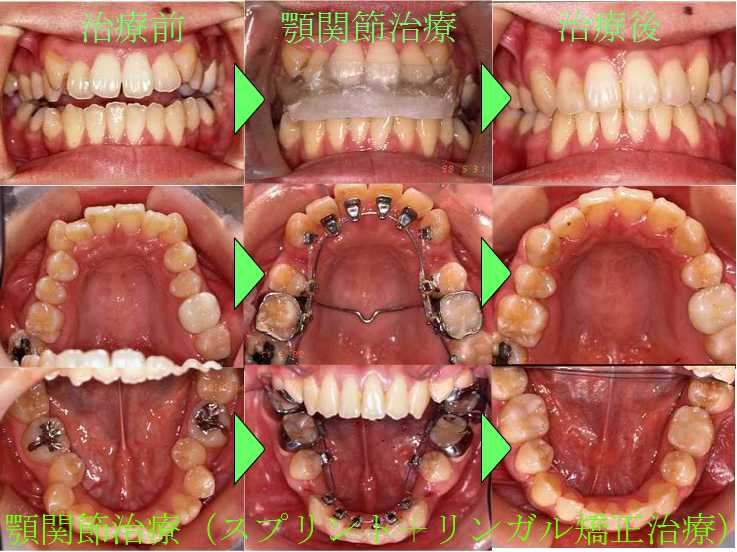

顎関節治療(スプリント+リンガル矯正治療)